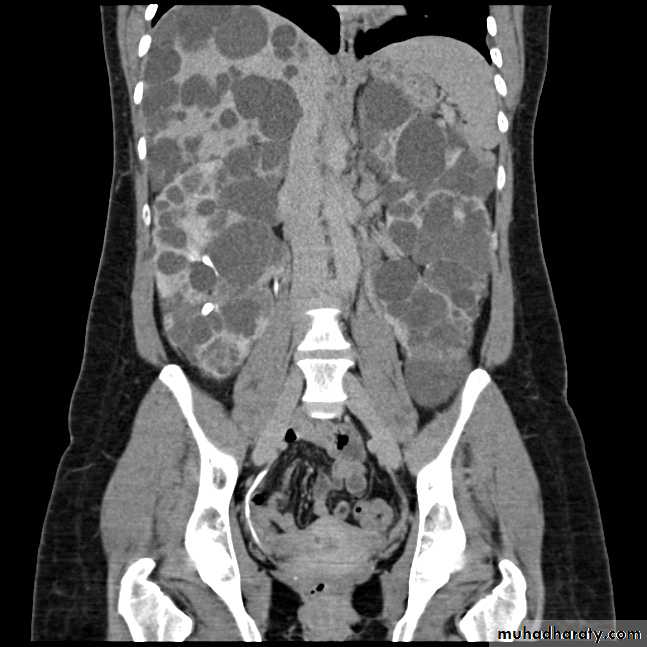

Polycystic renal disese in CT scan diffuse liver & kidney affection